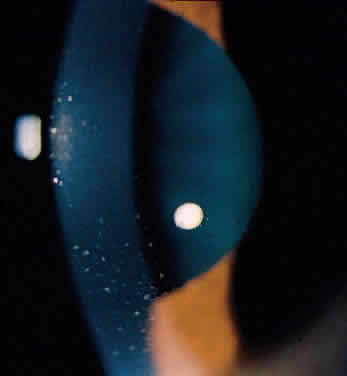

Ocular inflammatory changes include conjunctivitis, episcleritis, keratitis, acute and chronic iridocyclitis, and posterior changes as well.38–43 The acute iridocyclitis is milder and frequently not accompanied by as much pain, photophobia, and redness as in the acute iridocyclitis associated with other spondyloarthropathies. Mild injection of the conjunctival and episcleral vessels and blurred vision may be the only symptoms of an acute flare of activity. The endothelium of the cornea usually has cellular debris and poorly formed keratic precipitates in the lower cornea. The anterior chamber contains cells and moderate flare, and a protein clot is not infrequent in the pupil, with early formation of posterior synechiae (Fig. 6); however, the synechiae are usually more easily broken than in ankylosing spondylitis and Reiter's syndrome.44 Treatment with topical corticosteroids and mydriatics is usually effective. The activity of the iridocyclitis has been reported to follow the activity course of the inflammatory bowel disease. Systemic treatment of inflammatory bowel disease has been noted to help the ocular inflammation. Decreasing the systemic treatment occasionally allows ocular inflammation to become visible and requires close observation and appropriate increase in local therapy.39,44–46 Surgical resection of inflamed bowel for other medical reasons has sometimes been reported to coincide with lessening of ocular inflammation,44,46 but these observations need better evaluation.42 Posterior segment manifestations, including retinal and choroidal vascular disease, are also sometimes noted.47,48

Fig. 6. Partial posterior synechiae and fibrin clot in pupil with iridocyclitis and Crohn's disease.